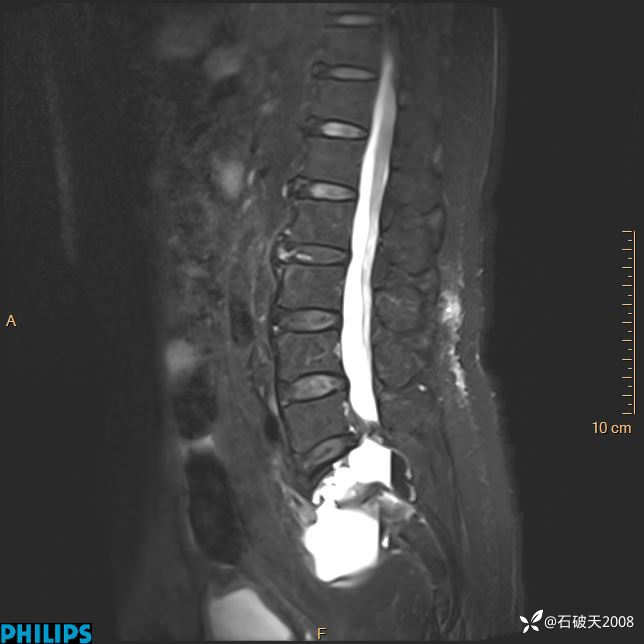

2023年3月份MRI影像

T2矢状位压脂